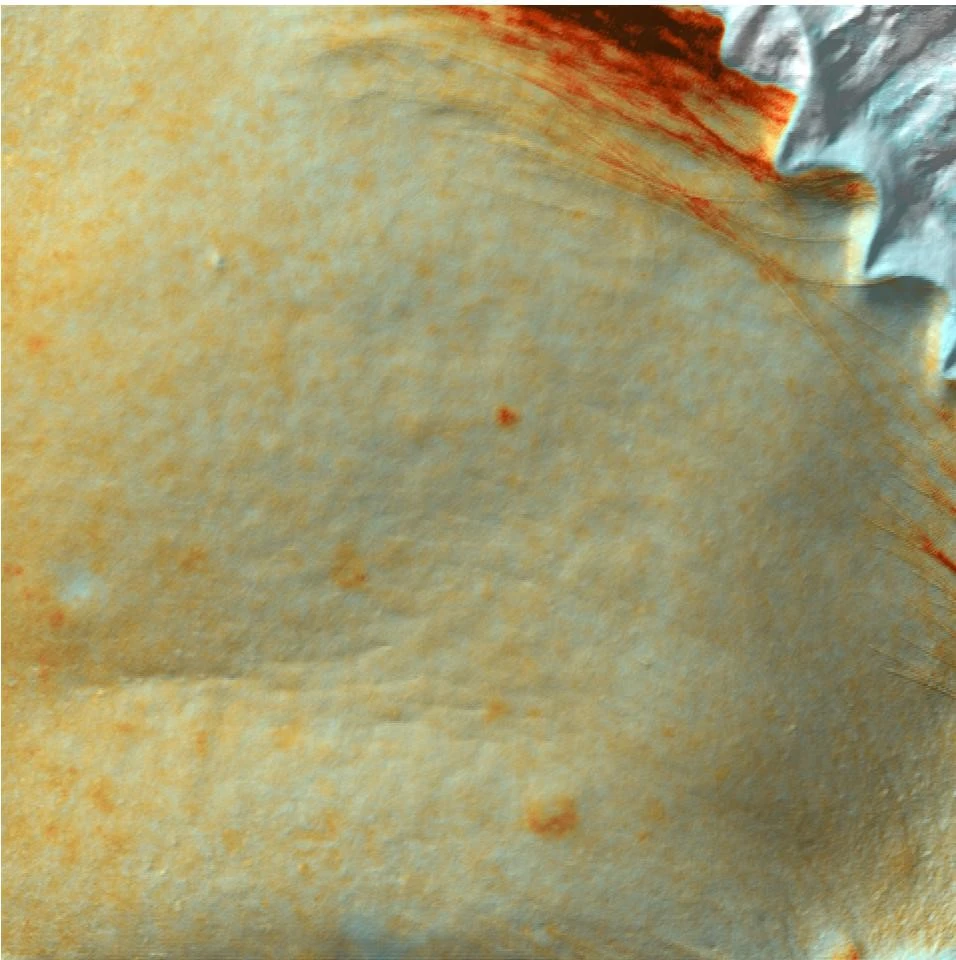

Также для фотодокументации клинических результатов был применен аппарат трехмерной визуализации поверхности кожи Antera 3D. Он предназначен для оценки состояния сосудистого компонента, интенсивности гиперпигментации, глубины залегания морщин различного калибра, ширины и количества пор, а также рельефа тканей. В данном исследовании использовалось документирование в режиме «меланин».

Комбинированный протокол IPL и Bellarti Hydrate

До терапии

После терапии